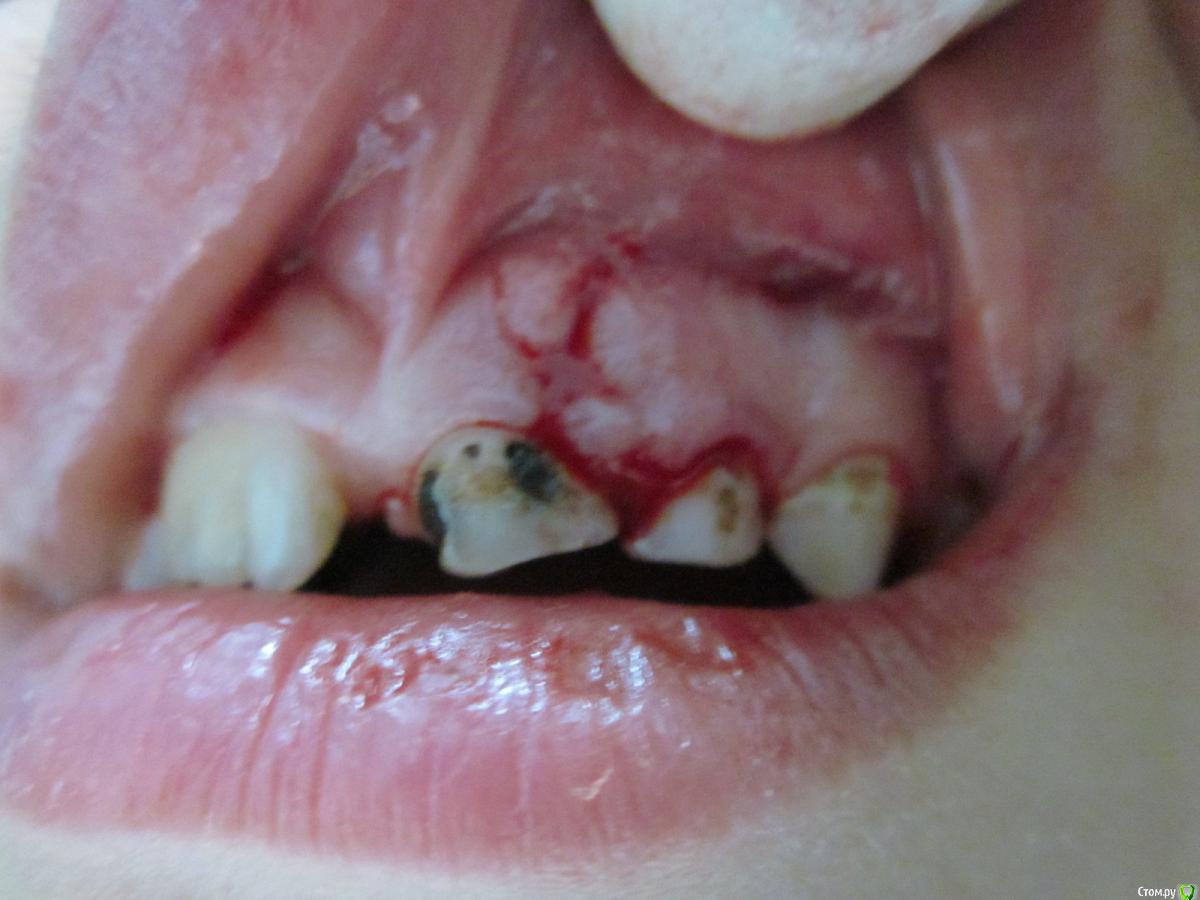

По данному случаю: пациент 6-7 лет, 21 не растёт, все динамят (ортодонты и терапевты), дошли до хирурга: на снимок прицельный, что то не то, на КТ охарактеризовал как одонтому. Операция под

анестезией Ультракаин дс, кортикальную пластинку трепанировал «расковырял» эскаватором, убрал конгломерат тведых тканей, саму оболочку, удалил 61. Биологический материал в пробирку с физ

раствором, направление на исследование в гистологию и ГОУ самим.